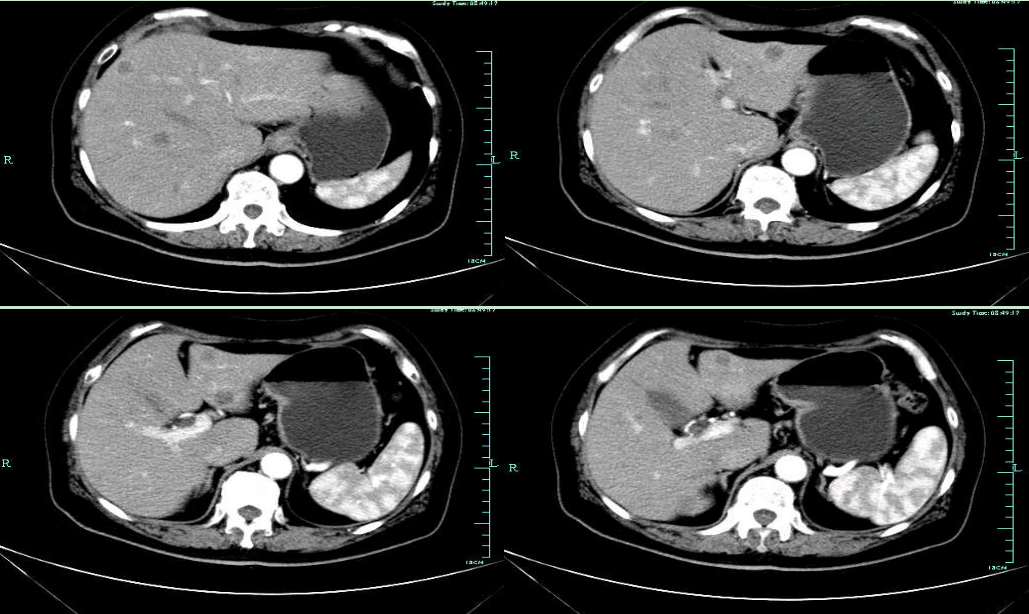

CT-H1

影像学检查结果评估:cPD。

疗效评估:cPR

TOGA研究是第一个使用HER2抑制剂曲妥珠单抗治疗不能手术的局部晚期、复发或转移的HER2阳性胃癌患者的Ⅲ期临床研究。TOGA研究结果显示,IHC2+/FISH阳性或者IHC3+的患者与对照组相比,OS分别为16.0个月和11.8个月(HR为0.65)。曲妥珠单抗联合化疗显著提高了HER2阳性晚期转移性胃癌的治疗缓解率和总体生存率。2012年8月,曲妥珠单抗治疗HER2阳性转移性胃癌适应症在我国获批。对该患者进行病理切片会诊,幸运的是其HER2检测为阳性。随即进行靶向联合化疗治疗,三个周期后,肝转移灶消失,曲妥珠单抗治疗效果显著。九个周期的靶向治疗联合放化疗后,疗效评估cPR,随即行手术治疗。